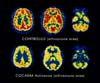

SPECT che compara i livelli di

attività tra il cervello di un soggetto sano e quello di un

soggetto eroinomane. Clicca sull'immagine per un

ingrandimento

PET che illustra l'attività

cerebrale in caso di dipendenza e nella sindrome

d'astinenza. Clicca sull'immagine per un ingrandimento

|